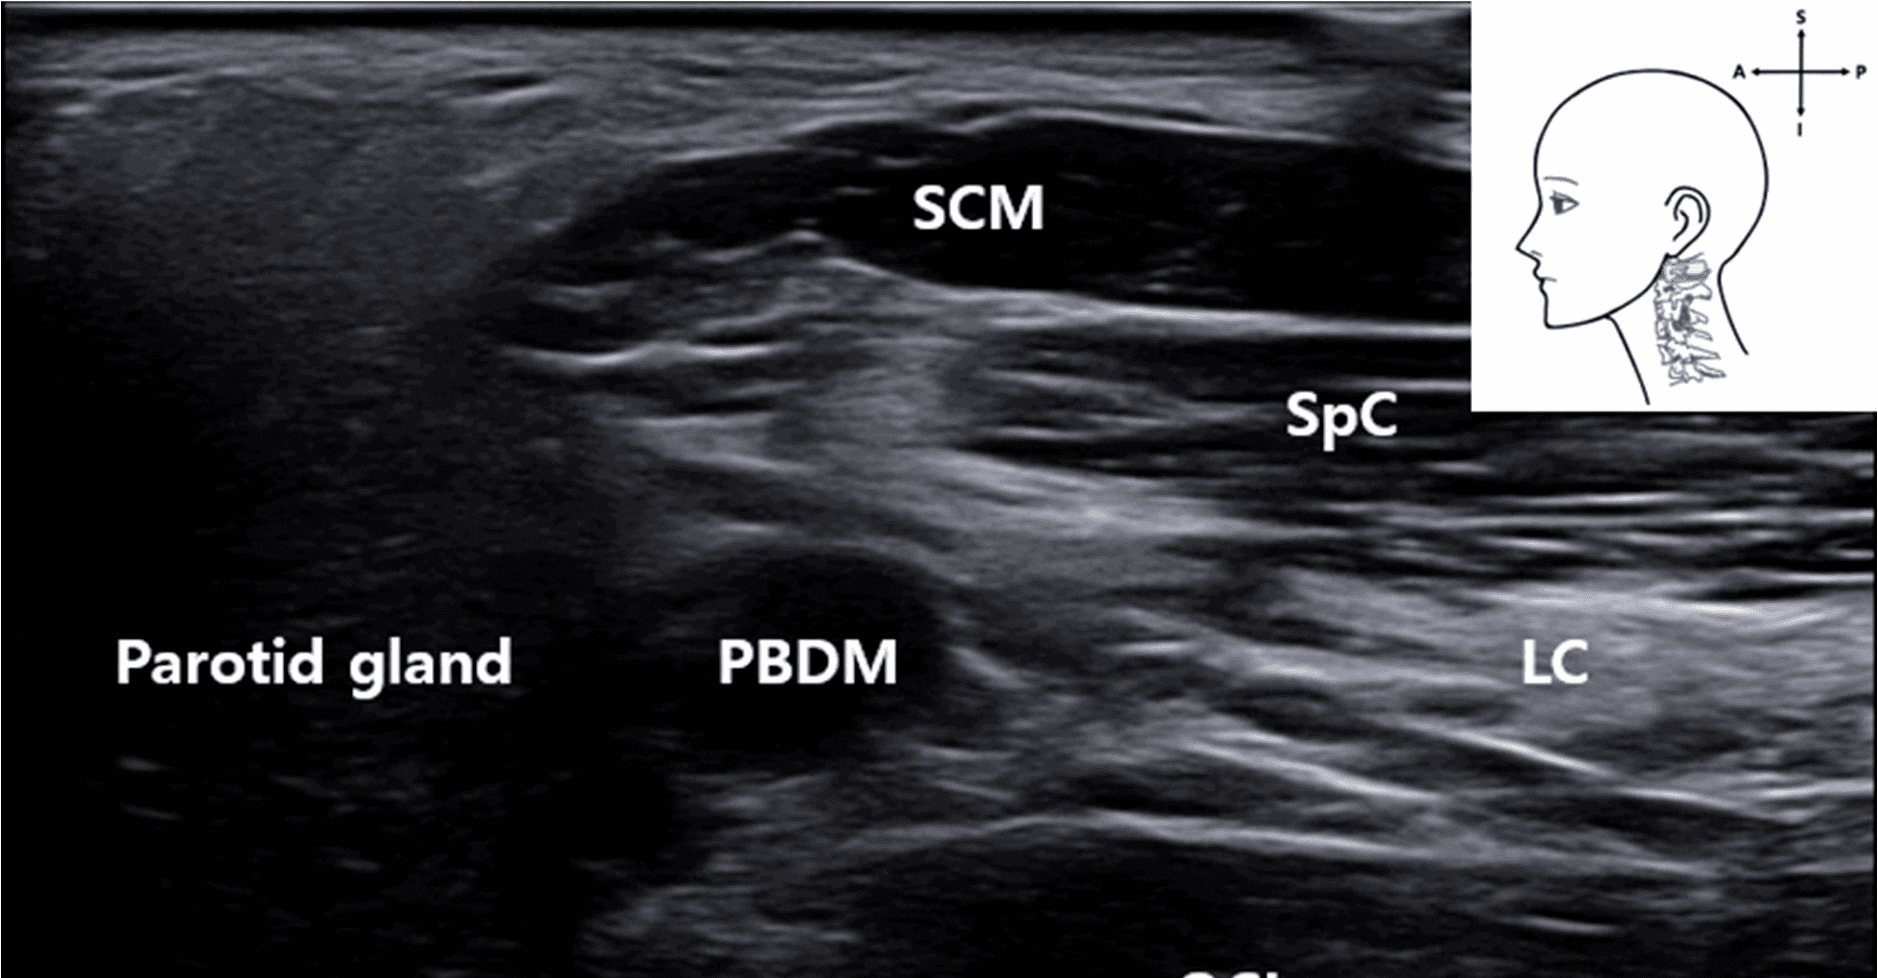

안면마비 - Ultrasound image showing the VA located deep between the posterior belly of the Figure 4. Ultrasound image showing the VA located deep between the posterior belly of the digastric muscle and occipital condyle. The SCM muscle lies superficially. This image was obtained with the probe tilted superiorly using a heel-toe maneuver to visualize the upper cervical region. SCM , sternocleidomastoid muscle; PBDM , posterior belly of digastric muscle; SpC , splenius capitis muscle; VA , vertebral artery; OC , occipital condyle; SP , styloid process; LC , Longissimus capitis muscle); blue rectangle, probe position.